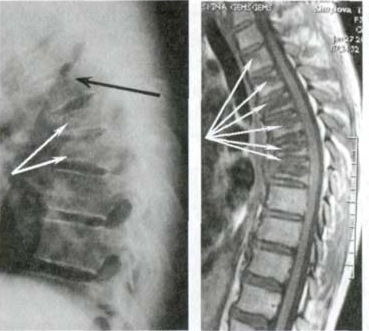

Podívejte se na tuto fotografii. Je to páteř člověka jen ve 44 letech, ale vypadá jako u starého člověka. Dříve se takové destrukce objevovaly po 60, dnes jsou běžné už u těsně nad 40. Tyto změny se s věkem zhoršují a jejich ignorování znamená riziko úplné ztráty pohyblivosti!

Bolesti a nepříjemné pocity v kloubech po 40–50 letech téměř ve 100 %

případů ukazují opotřebení a ničení chrupavky.

Ale bolesti zad jsou obzvláště nebezpečné — kvůli zvláštní stavbě

chrupavky a meziobratlových plotének dochází k úplnému opotřebení

chrupavky 3–4× rychleji!